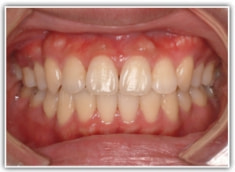

治療後(2年6ヶ月後)

治療後のセファロ分析

前歯の位置、傾斜、Eラインなど、改善が認められます。

治療後のセファロ分析正貌

非対称が解消されております。